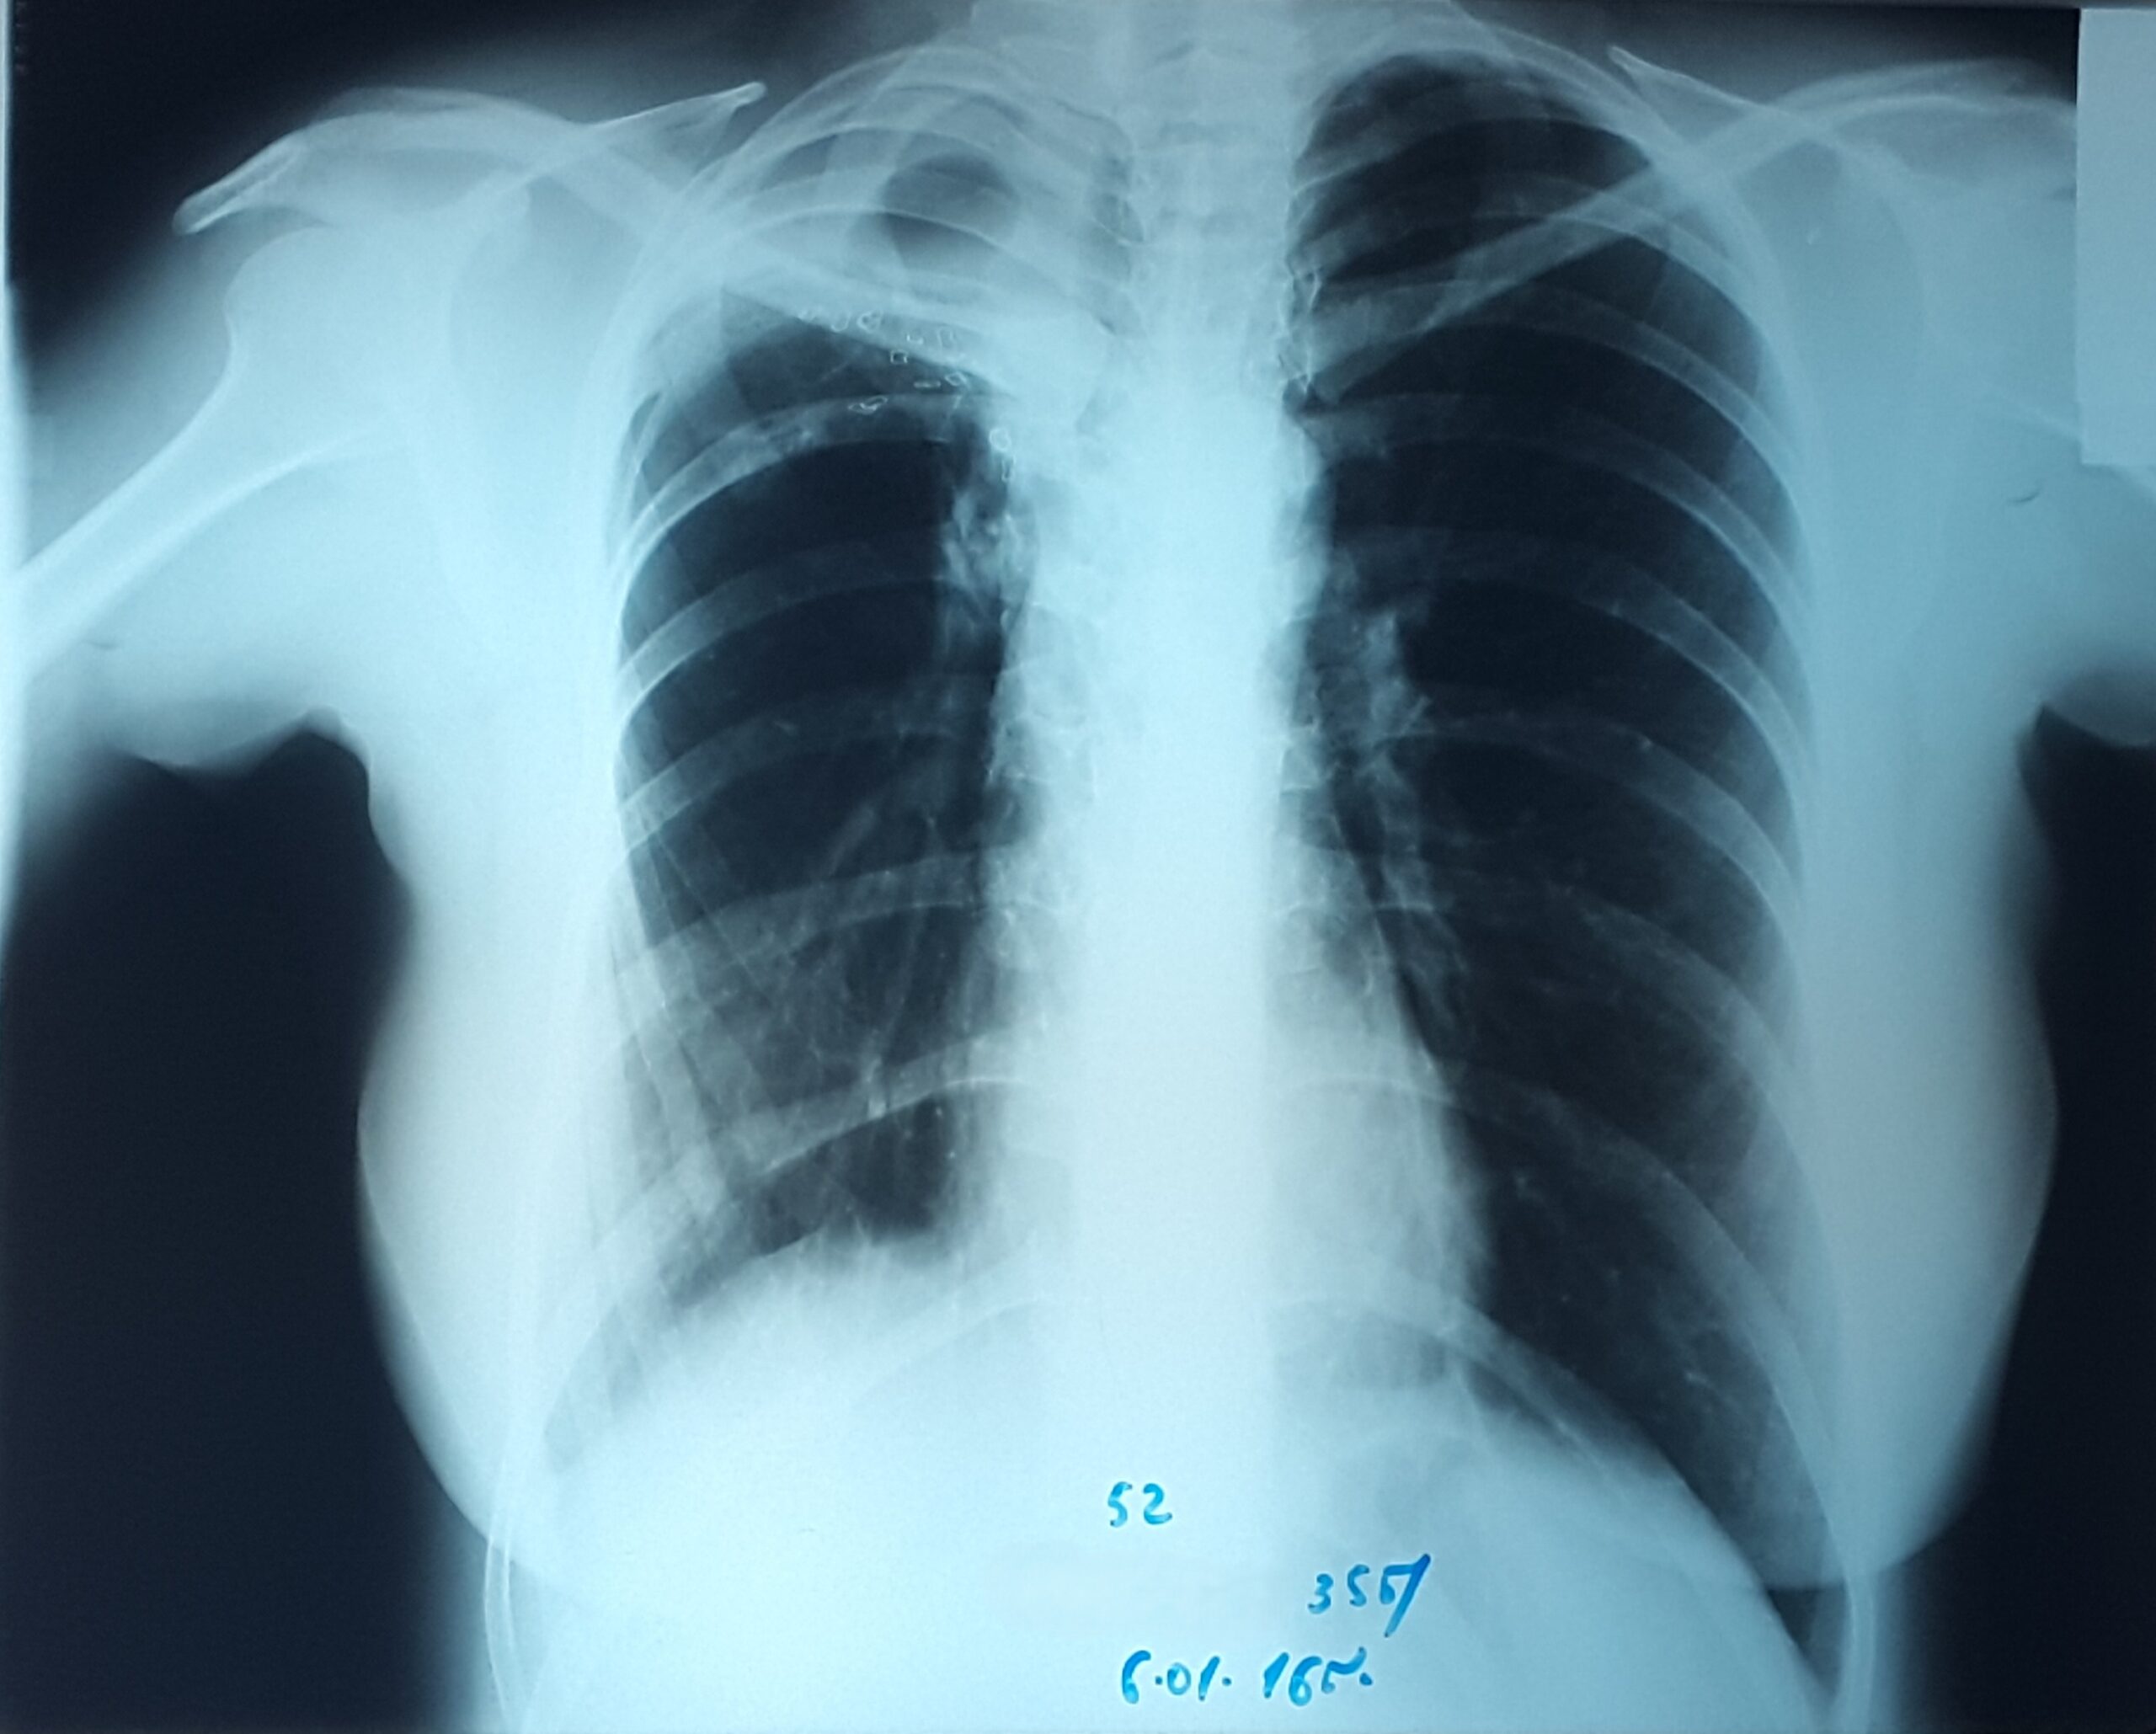

პაციენტი 37 წლის ქალი. 1997 წ-ს გაკეთებული აქვს მარჯვენა ზედა წილის რეზექცია ფილტვის ტუბერკულოზის გამო. წლების განმავლობაში აქვს გამწვავებები, რაც გამოიხატება მაღალი ცხელებით, ხველით, დიდი რაოდენობით სისხლნარევი, მძაფრი სუნის მქონე ნახველის გამოყოფით. რენტგენოლოგიურად ინახა დიდი ზომის ღრუ მარჯვენა ფილტვის ზედა ველში. ბრონქოსკოპიით ინახა დიდი ზომის მარჯვენა ზ/წილოვანი ბრონქის ტაკვის ფისტულა. ტაკვის სიგრძე იძლეოდა ბლოკატორის ჩადგმის შესაძლებლობას. რიგიდული ბრონქოსკოპით მარჯვენა ზ/წილოვან ბრონქში ჩაიდგა MEDLUNG-ის ბლოკატორი N13. რამოდენიმე საათში საჭირო გახდა ბლოკატორის გამოცვლა ნაკლებ (N12) ზომაზე განვითარებული მარჯვენა ქვედა წილის ატელექტაზის გამო. მანიპულაციის შემდეგ პაციენტს შეუწყდა სისხლნარევი და ჩირქოვანი სეკრეტი. 10 თვის შემდეგ საკონტროლო გამოკვლევით ღრუს ადგილას დაფიქსირდა ფიბროთორაქსი. უახლოეს მომავალში, გულმკერდის კტ კვლევის შემდეგ, იგეგმება ბლოკატორის ამოღება.